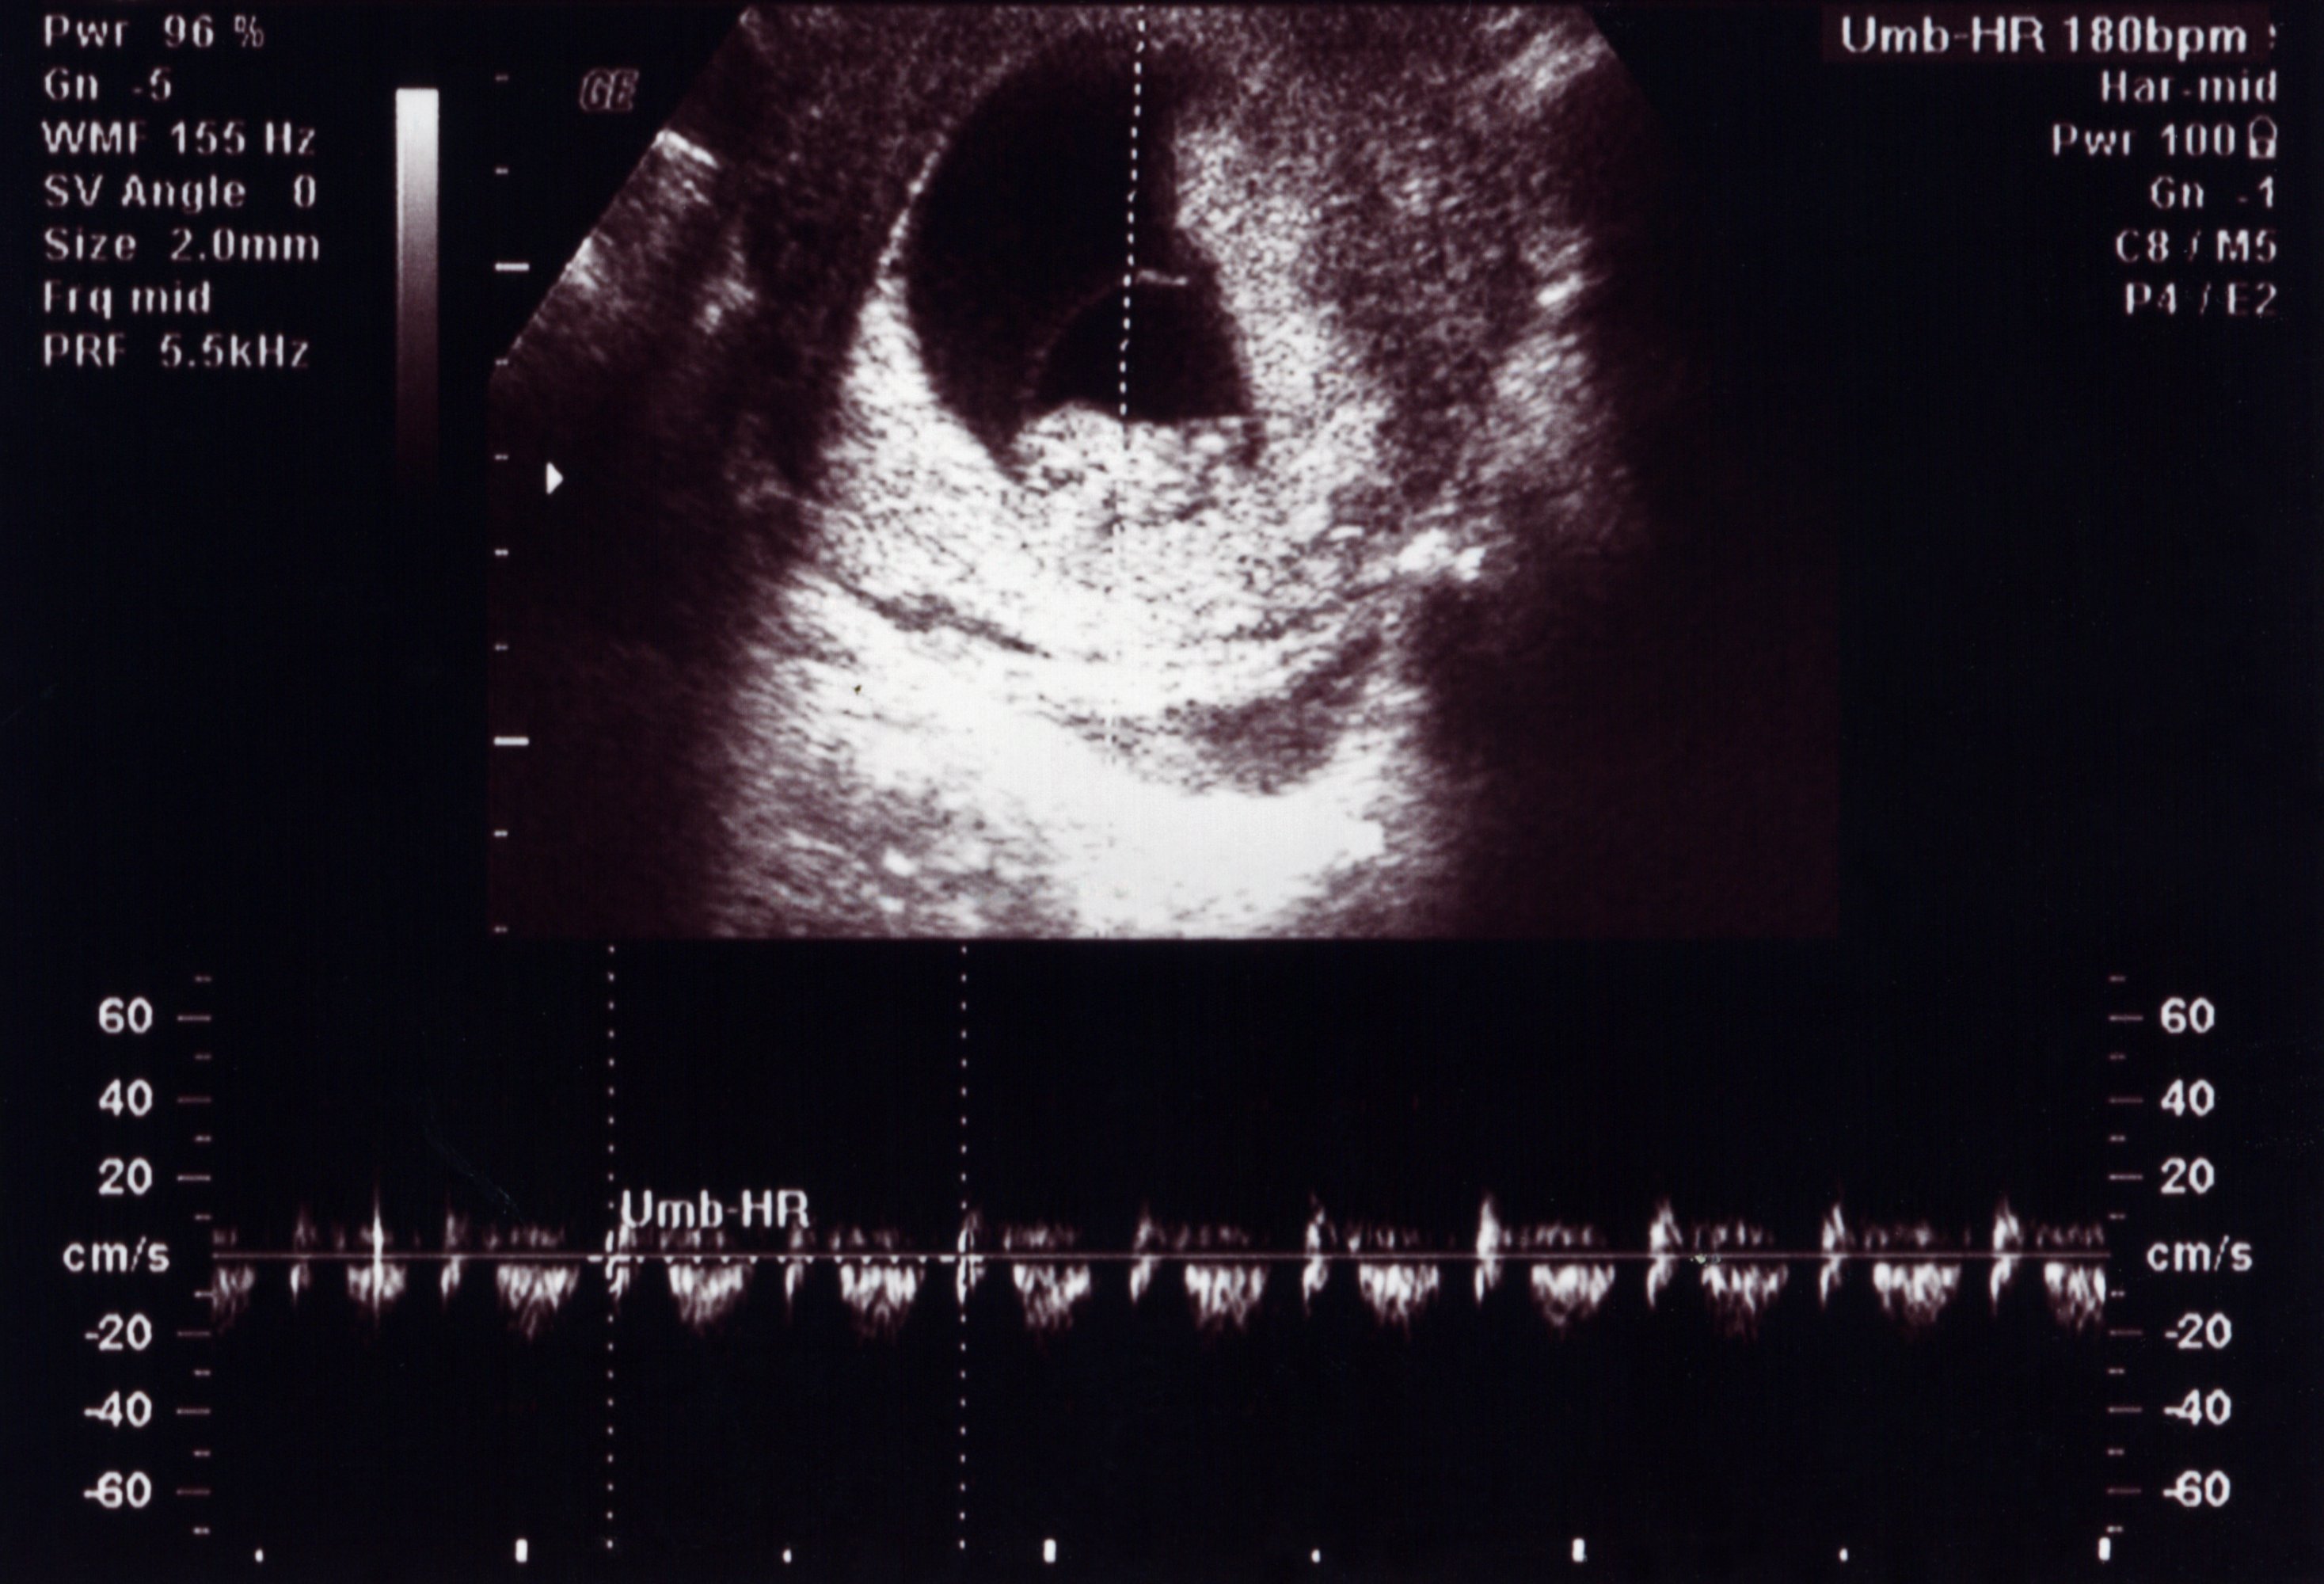

На этой стадии беременности ребенок становится все более осознанным и активным. Узи фотографии показывают, что его плодовой мешок становится уже образованным, а сердцебиение можно услышать с помощью узи аппарата.

Хотя пока еще рано говорить о половой принадлежности ребенка на узи фото, уже можно увидеть формирование его черт лица. Глаза, нос, губы - все более четко проглядывается на узи снимках.